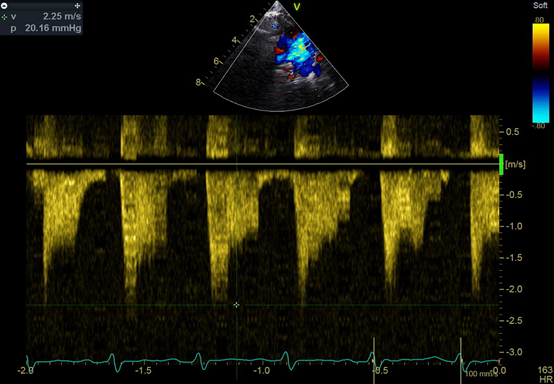

An echocardiogram showed a large ventricular septal defect overriding the aorta with septum and quadricuspid aortic valve (Figure). No stenosis or regurgitation was observed though the valve. The valve consisted of 3 equal cusps and a smaller one, which is type B according to the Hurwitz and Roberts classification (Video). Fluorescent in situ hybridization was negative for 22q11 deletion. The patient established feeds and was discharged home with the plan to have regular follow-ups.